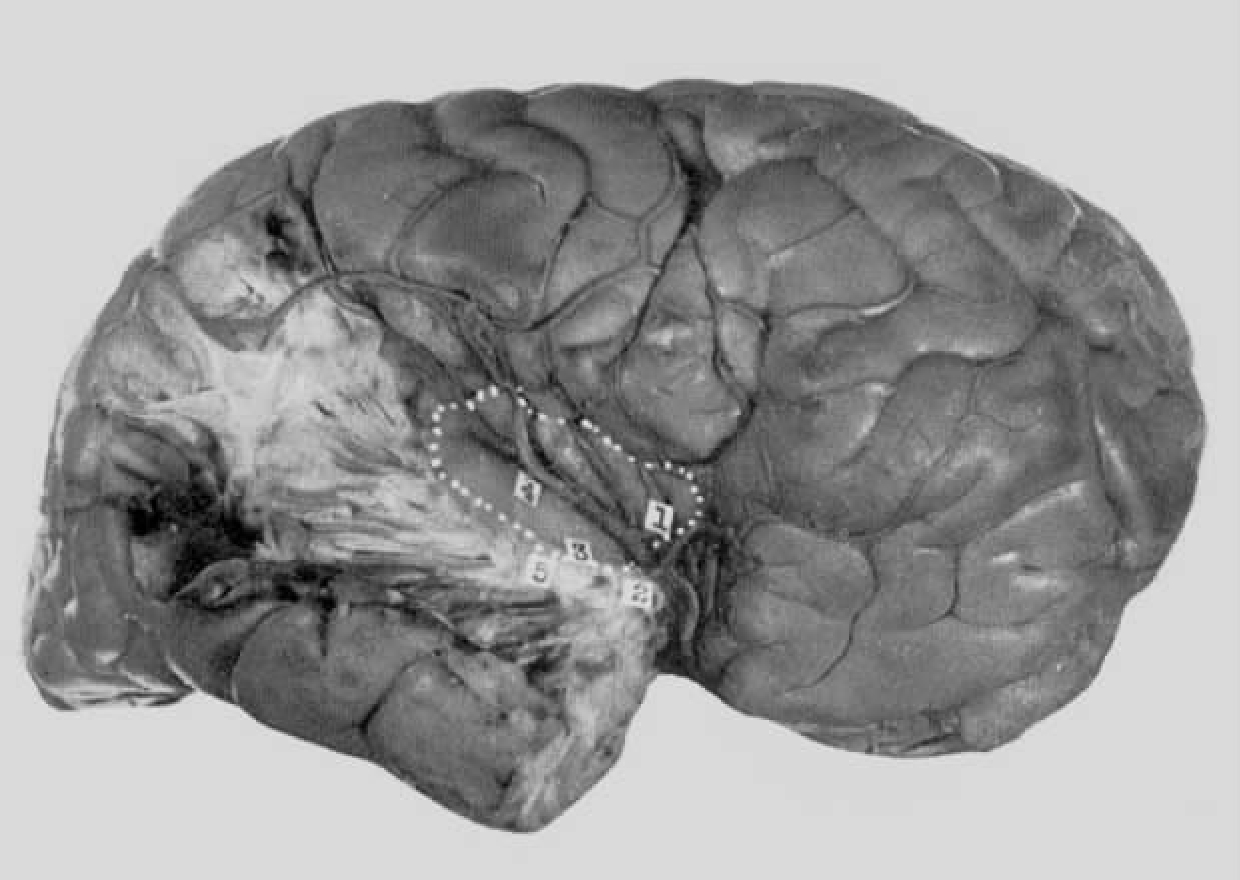

气脑造影术显示:脑室扩大,右侧颞角的下端较左侧大。

图4-5 病例D.F.术前准备(已画好骨瓣切除的范围,所示的交叉点指癫痫灶)

脑电图测量在患者停药24小时后执行,偶尔可见棘波出现,波形时紊乱时规则。频率在2到4Hz之间,偶尔为6Hz。右侧咽部的电极可记录到反相波,其他处则无。临床和电记录证据似乎提示癫痫灶位于右侧颞叶或脑岛深处。

行右侧开颅术(图4-5)。除了近外侧裂处的小范围萎缩(图4-6箭头所指处)外,大脑初看起来完全正常。在手术过程中发现,脑岛前方第一颞回处存在萎缩区,该区扩展到脑岛下方的环岛叶灰质中,甚至侵入颞叶后表面,延及海马钩。损伤可能源自她5岁手术时全麻术所致的缺氧。

刺激部位

右脑,近中央沟及脑岛处(见图4-6和图4-7)。

图4-6 病例D.F.右大脑半球外侧面(白色虚线为中央沟和外侧裂,点19示颞叶最前部)